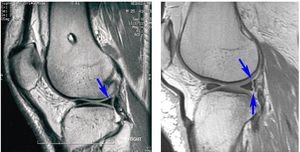

• MR. Това е най-важният диагностичен метод за определяне на степента на увреждане.

За да се улесни диагнозата на ЯМР, лекарите използват класификацията на увреждане на менискуса на Столер. Тази класификация е кръстена на нейния разработчик Дейвид Столър.

Основната класификация според Столер е критериите за тежестта и степента на увреждане на менискусната тъкан. Лекарят разкрива степента на дегенерация на хрущяла от разпространението на сигнала, промяната в неговата интензивност и местоположението на промените.

Според тази класификация има 4 степени на повреда:

• Нулева степен. По време на изследването лекарят не вижда промени в хрущяла. Платовете са в добро състояние.

• Първа степен. ЯМР разкрива сигнал с повишена интензивност, но фокусът му не е в контакт с повърхността на хрущяла.

• Втора степен. По време на изследването се открива мощен линеен сигнал. Все още не докосва повърхността на менискуса, което означава поддържане на неговата анатомична структура. Няма пълно разкъсване на тъканта, но нейната цялост е нарушена.

• Трета степен. Силата на сигнала значително се увеличава. Той достига до повърхността на менискуса. Това означава, че структурата на хрущялната тъкан е нарушена. Възможно е пълно отделяне на менискуса с офсет.

Класификацията на Stoller се прилага само при използване на магнитен резонанс. Опростява разработването на тактики на лечение.